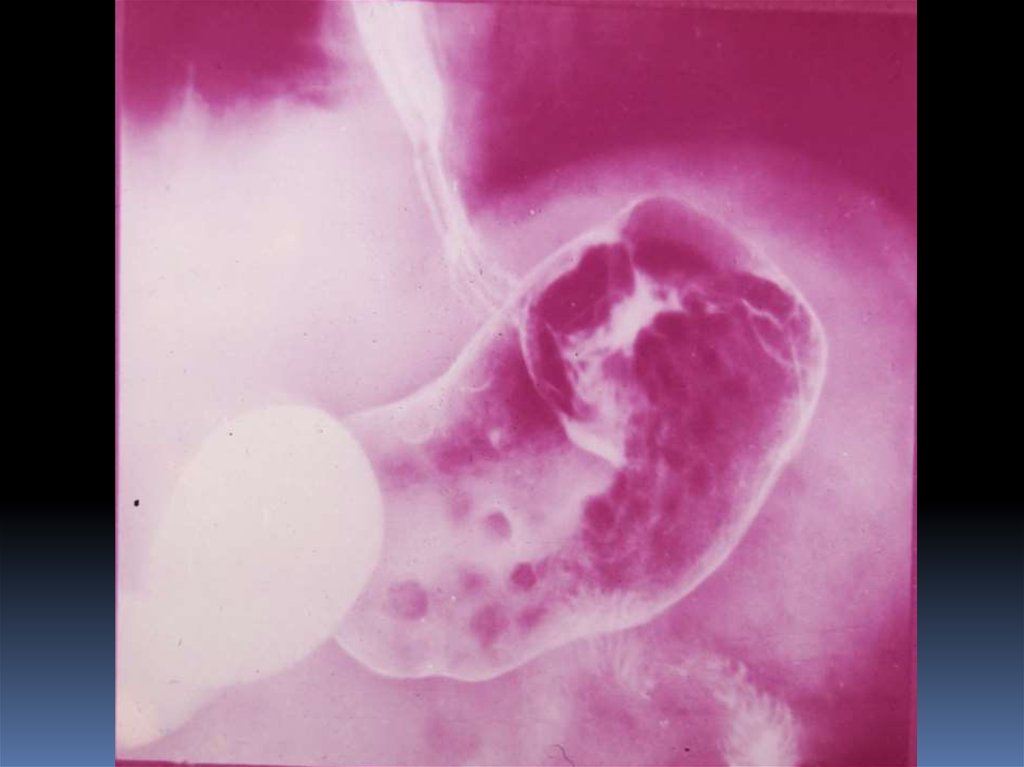

17. Классификация рака органов ЖКТ

1. Экзофитная форма:

2. Эндофитная форма:

узловая форма;

диффузноинфильтративная

форма;

полипоподобная

чашеподобная форма. инфильтративноязвенная.

3. СМЕШАННАЯ ФОРМА – 10-15%